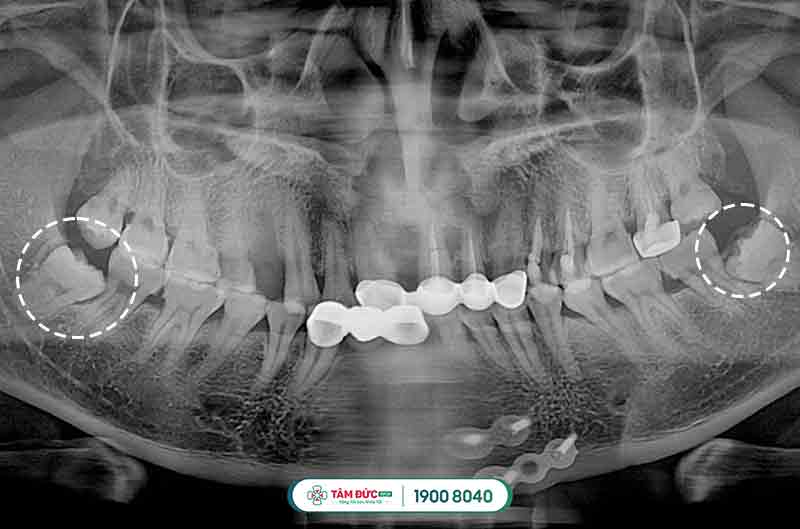

1.1 Các dạng răng khôn mọc lệch thường gặp

- Răng khôn mọc lệch má.

- Răng khôn mọc ngược vào phía xương hàm.

- Răng khôn mọc lệch và kẹt vào răng số 7.

- Răng khôn mọc ngầm trong xương hàm.

2.3.1. Tiến hành chụp phim X-quang

Chụp x-quang chiếc răng khôn mọc lệch để xác định vị trí, cũng như hướng mọc răng như thế nào rồi đưa ra phương pháp nhổ bỏ thích hợp nhất.